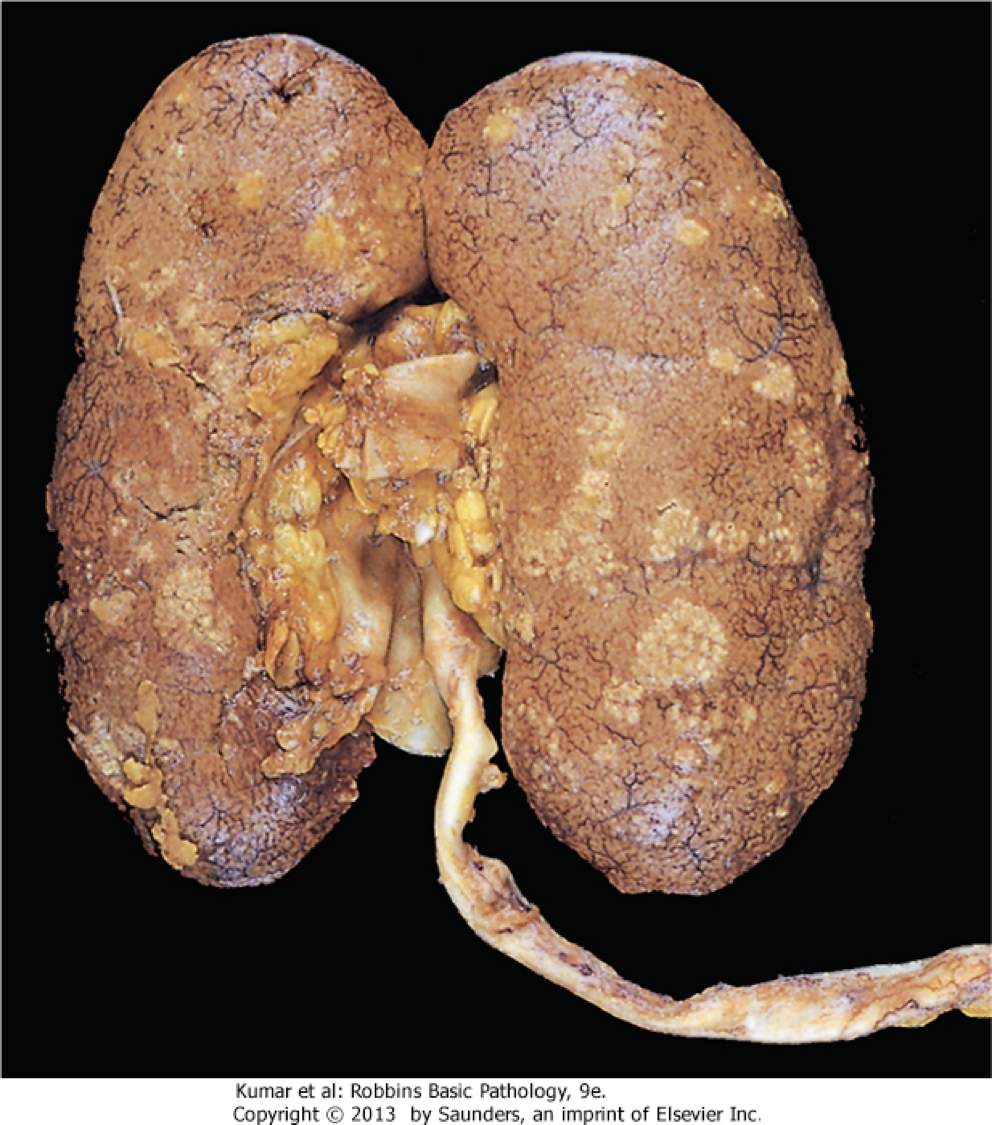

What is wrong with it? (this is one kidney cut in half and opened like a book, but we are seeing the capsular portion)

This is a fixed kidney demonstrating acute pyelonephritis